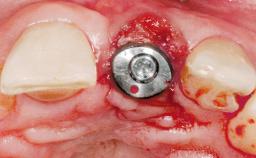

Immediate Placement of an Implant in a Maxillary Right Central Incisor Site

A 30-year-old female patient was referred to the office for the treatment of tooth 11. Her chief concern at the initial visit was to inquire, “Why is my tooth pink?” Upon clinical examination, it was determined that tooth 11 had a previous history of trauma and that the clinical crown had become noticeably pink in color as a result of internal resorption. This diagnosis was confirmed radiographically, indicating a large radiolucency involving the central and distal portions of the clinical crown. It was determined that restoration of this tooth was not possible, and that extraction was indicated. The presence of a mid-line diastema, which the patient wanted to reproduce, directed the treatment plan for tooth replacement utilizing a dental implant.

Type of Implants One-Piece|Reduced-Diameter

Placement Protocol Immediate implant placement

Tooth Site Maxillary incisor or canine

Socket Morphology Single-root socket

Socket Integrity Sufficient, with intact bone walls